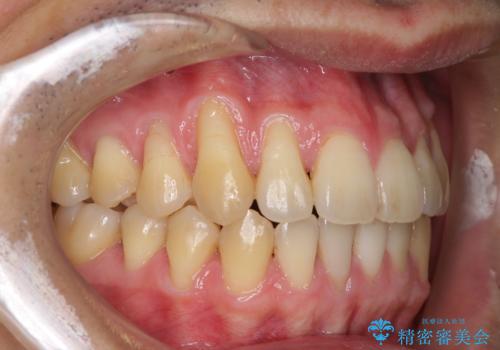

- 上下の前歯の反対咬合を気にして来院された患者様です。

インビザラインを用い、下顎はIPR(歯と歯の間を削る)と歯列全体を後方に移動させ、上顎は前歯を持ち上げることで、反対咬合を改善していくこととしました。

八重歯の歯根が見えている点も気になっているので、矯正歯科治療後に歯肉移植による根面被覆を行うこととしました。

インビザラインによる反対咬合の改善は、上の歯が下の歯を乗り越えていく期間に咬み合わせが非常に不安定となり、治療が長期化することがあります。

また、ワイヤー矯正と異なり歯軸改善の強い力を前歯にかけるため、反対咬合で裏側にある歯の歯肉が退縮しやすくなります。